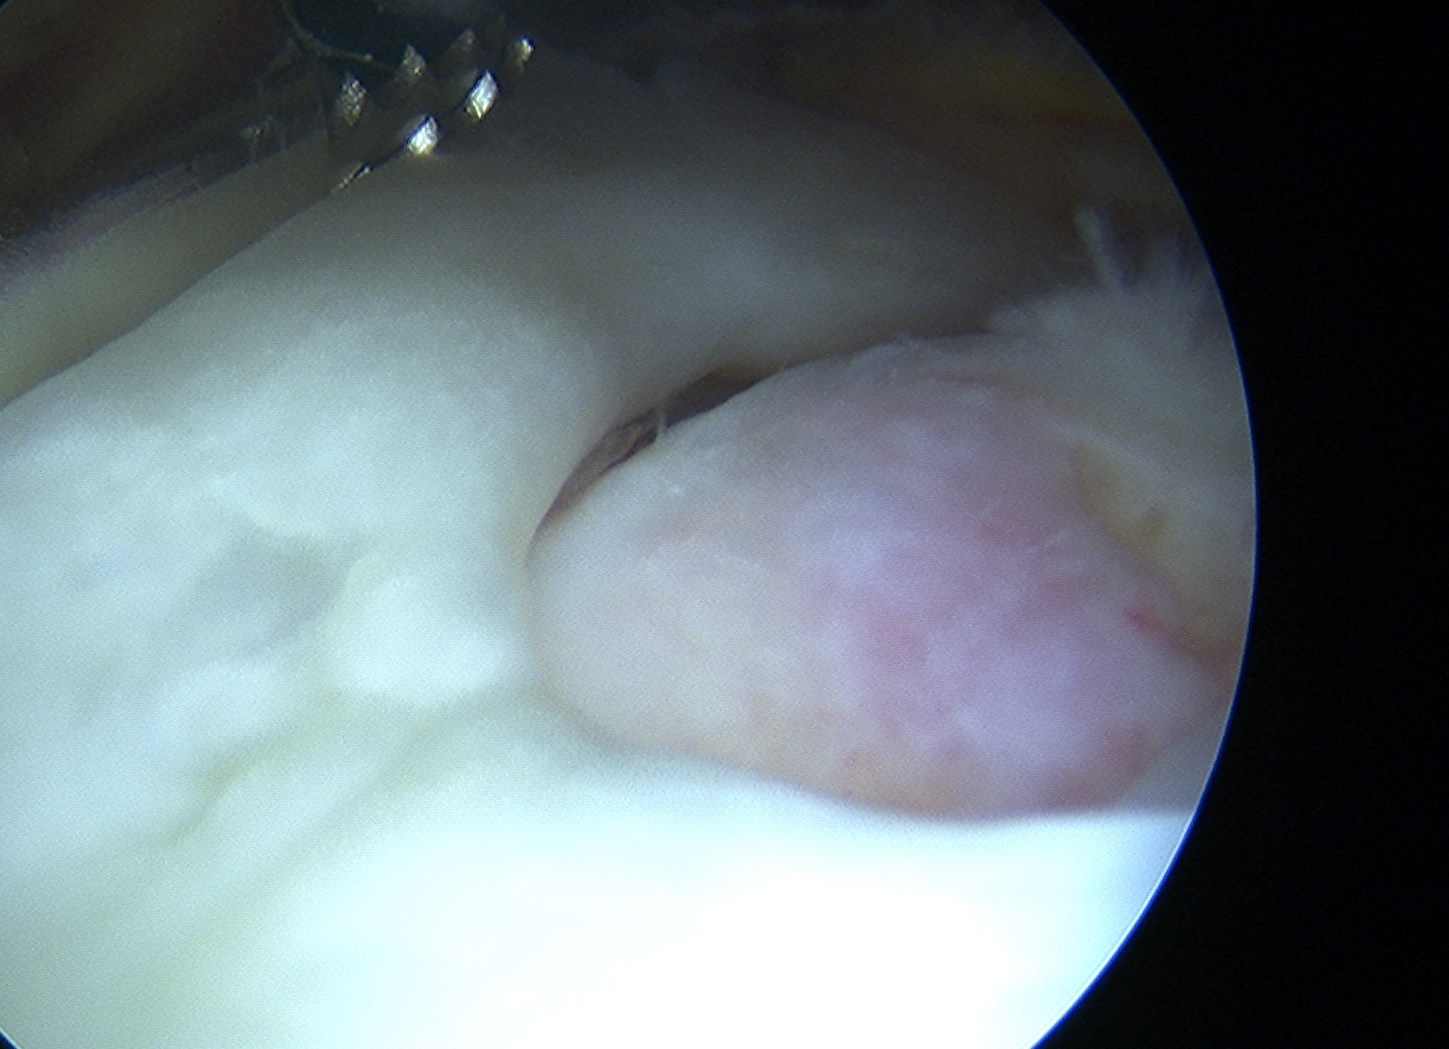

Arthroscopy

Tear patterns of supraspinatus and infraspinatus

| Crescent shaped | U shaped | L Shaped |

|---|---|---|

|

Small to medium tears Repair to footprint |

Large tears Need margin convergence then repair to footprint |

Antero-superior or postero-superior tears Need to mobilize cuff anterior or posterior |

|

|

|

Crescent, U shaped and massive rotator cuff tears